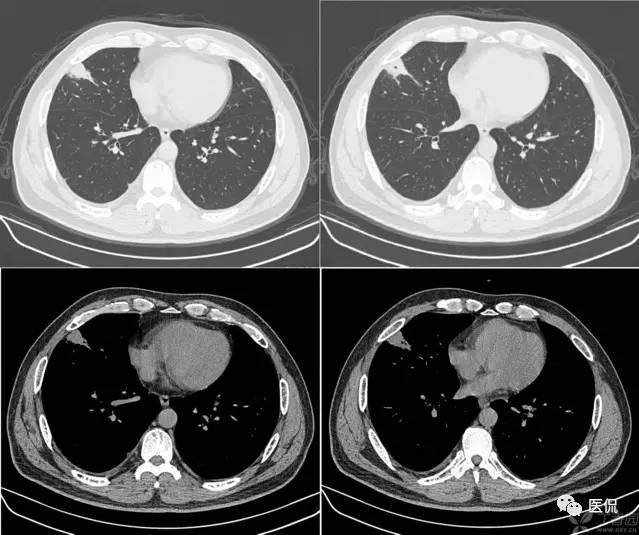

桃尖征

指肿块某一边缘尖角状突起形似桃尖,是炎性假瘤包膜的粘连牵拉,为良性肿块尤其是炎性假瘤特有。由于肿瘤大多位于肺的浅表部位,邻近胸膜常出现炎性反应,继之局限性的胸膜增厚、粘连,于肿物边缘可见类似胸膜幕状粘连的尖角状表现,这种尖角和肿块连在一起酷似一个桃子的桃尖。假瘤的主体和胸膜的炎性牵拉形成的尖角常常和周围胸膜、心包及纵隔粘连形成桥样结构及宽桥征;炎性假瘤的形成,一般被认为是感染后非特异性炎症的机化修复而引起的局限性慢性瘤样增生,形成的肿块压迫周围肺组织周围组织反应性改变,形成假包膜,所以一般边界广整,少数包膜不完整、无包膜或有胸膜粘连者,边缘可不光整。炎性假瘤依据细胞成分为组织细胞瘤型、硬化血管瘤型、浆细胞肉芽肿型、细胞上皮乳头痒增生等五个类型。肿块形态不规则和肿块分叶是病灶在病理上不同组织、不同数目因而生长速度不同所致;而边缘光滑的炎性假瘤则是同类组织以同等的生长速度增生形成。假瘤的分叶一般较浅或没有分叶,多为单发,两肺各叶均可发生,右侧多于左侧,下叶多于上叶。炎性假瘤可以有如下表现:

炎性假瘤桃尖征:

炎性假瘤(病灶形态不规则,边缘可呈刀切样,周围可见毛玻璃样改变,强化异常明显):

炎性假瘤(病灶边缘多发性空泡,表现为病灶边缘部位类圆形的光整的气体样低密度,是尚未被病变替代的肺结构支架,或病变坏死,这种空泡多位于病灶的边缘):